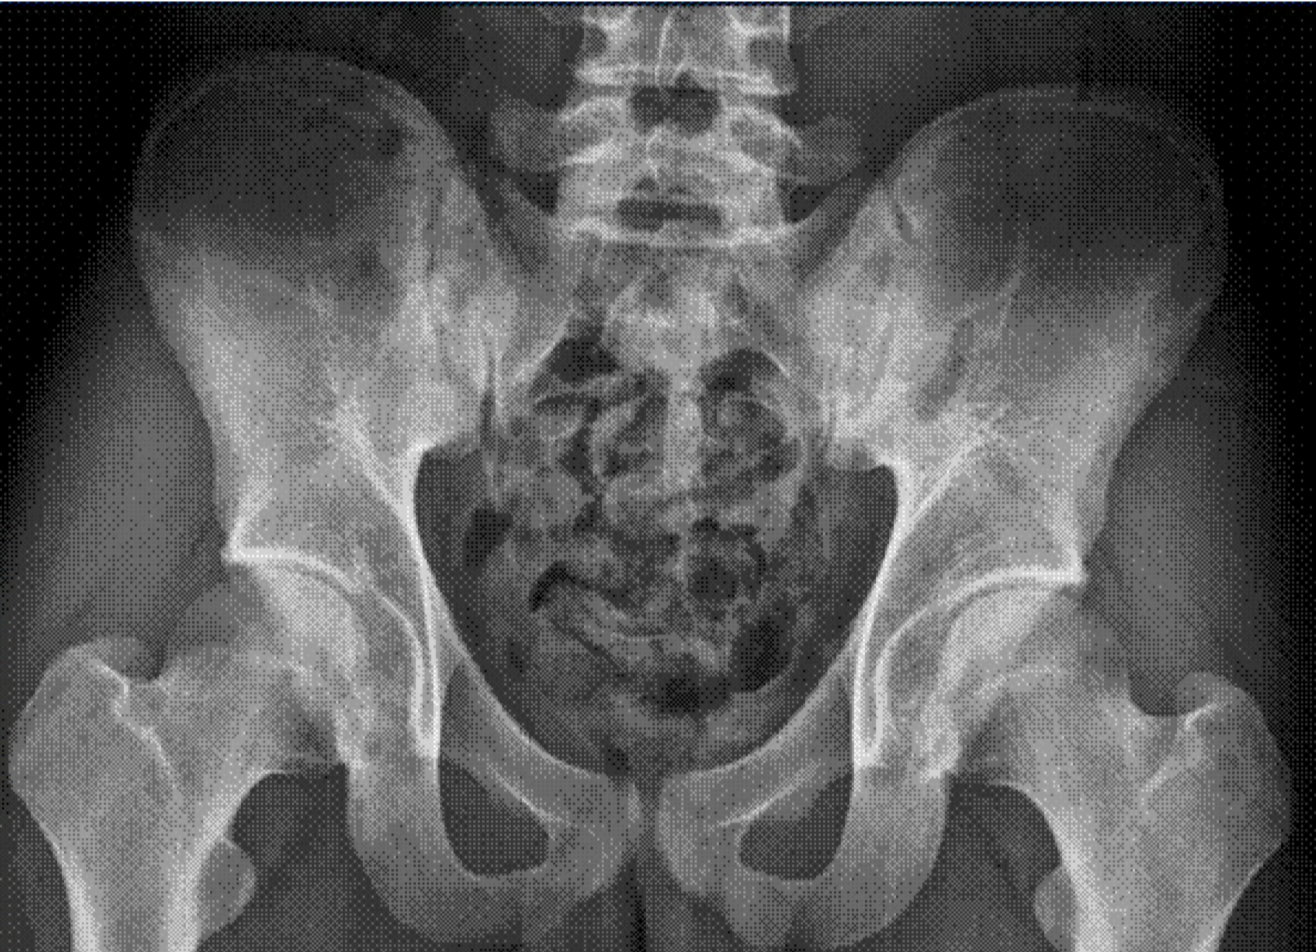

In urinalysis, the microscopic white blood cell count was 1–4 cells/high power field (HPF), many red blood cells and proteins were observed, and 24-hr urine protein level was 451 ㎎. The random urine protein/creatinine ratio was 287 ㎎/g. Mild bilateral sclerotic changes of the sacroiliac joint were observed on a pelvic radiograph.On renal U/S, the right kidney was 10.41 ㎝ and the left kidney was 11.07 ㎝, both within normal range, and no abnormal findings were observed in the renal parenchyma. However, a 0.9-㎝ calculus was observed in the Rt. kidney.